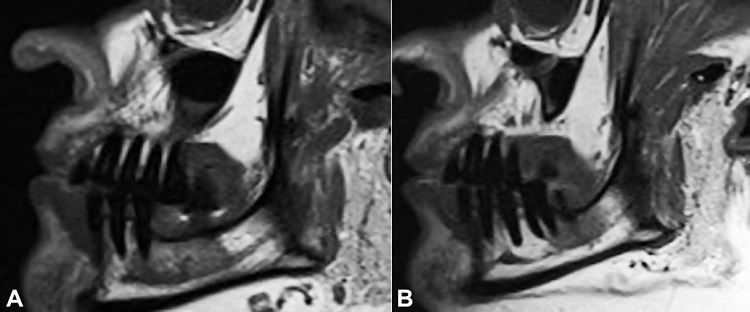

As a result of the patient’s complaint, we identified a small area adjacent to the region of the right mental nerve that was uncomfortable on palpation. No other changes were found by means of cone-beam computed tomography (Figure 2A) and clinical examination. Magnetic resonance features made possible to identify a change in the mandibular body extending to the entire right side (Figures 22C, 33B), coinciding with the clinical complaint, indicating a probable mandibular medullary invasion.